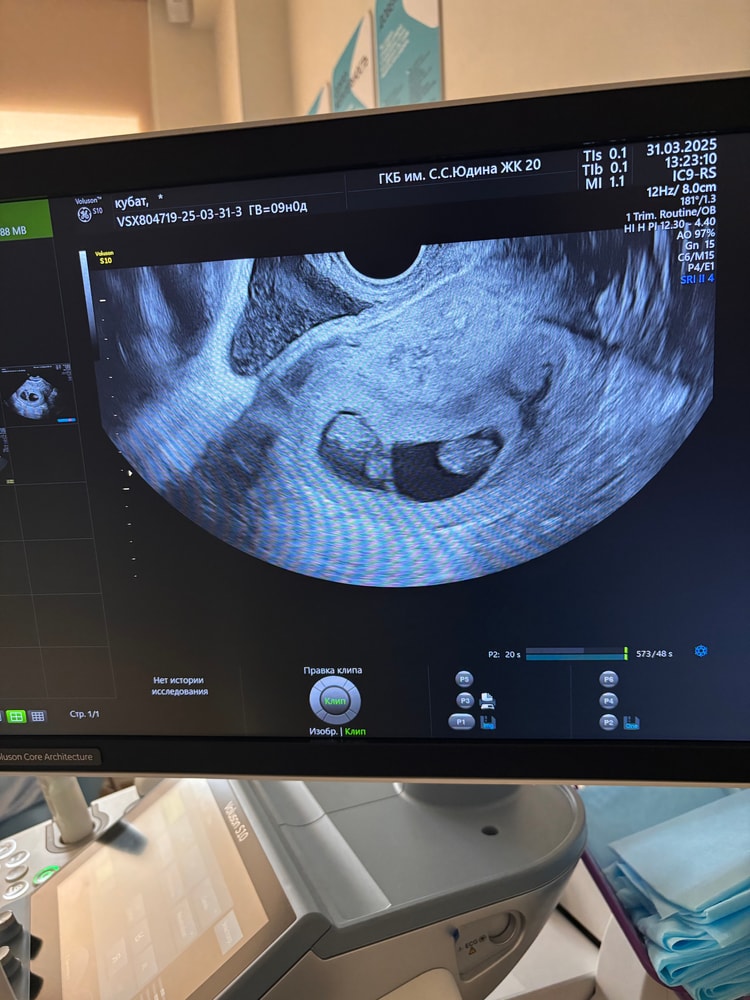

На 5й неделе беременности подтвердилось что у меня двойня🥰 спустя 2недели повторно делали узи на 7й неделе, есть сердцебиение у обоих. И сказали есть киста небольшая и пока понаблюдаем. Но мне кажется или не знаю вообщем посмотрите на фото. Могут ли не заметить третьего и сказать что это киста? У кого нибудь так было? Так надеюсь что это не киста🙏 пишите что думаете, пожалуйста

Перепутать в 7 недель пя и кисту... Мало вероятно

Больше было бы вероятно, если бы ничего не нашли, а там вдруг 3. Если говорят что киста, все же вероятнее она. Но точно узнаете через пару недель)

Я тоже склонна верить врачу, я бы на вашем месте надеялась на кисту, которая сама рассосется, чем на тройню, это ж практически невозможно выносить нормально